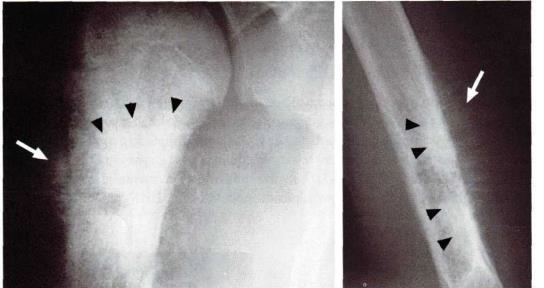

Analise a radiografia, abaixo:

Reação periosteal em pacientes com osteossarcoma do úmero (setas). A maior densidade radiográfica na metáfise e diáfise umeral está relacionada com a matriz óssea da lesão (pontas de setas).

Assinale a alternativa que preenche, corretamente, a lacuna do texto: